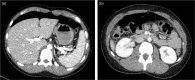

We report the first pediatric use of a laparoscopic-assisted endoscopic overstitch technique for managing an acutely perforated gastric ulcer in a 16-year-old female. The patient presented with symptoms consistent with gastrointestinal perforation, confirmed by radiologic pneumoperitoneum. Diagnostic laparoscopy identified inflammatory adhesions and a gastric ulcer perforation. Concurrent endoscopy precisely located the defect, which was effectively closed using an endoscopic overstitch device mounted on a therapeutic double-channel gastroscope. Closure involved three full-thickness inverted figure-of-eight sutures, verified by an intraoperative leak test and reinforced with an omental patch. Postoperative recovery was rapid and uncomplicated, progressing to a regular diet within 3 days. This innovative hybrid laparoscopic-endoscopic technique demonstrates efficacy, safety, and the benefits of minimally invasive surgery for pediatric gastrointestinal perforations, emphasizing its potential superiority over traditional methods.